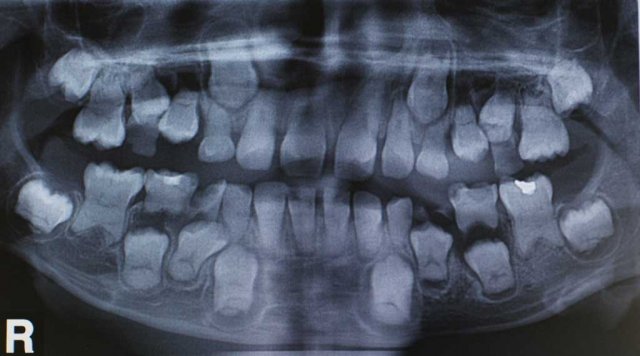

Εργασίες Γέφυρες Εμφύτευματα 3d-Modeling Ενδοδοντικές θεραπείες Παιδιά Καθαρά δοντάκια !!! Χαρούμενα παιδάκια Ακτινογραφική εικόνα μικτής οδοντοφυία ( ύπαρξη ταυτόχρονα μόνιμων και παιδικών δοντιών στο στόμα) σε παιδιά ηλικίας 6 με 12 ετών. Published on June 24th, 2021